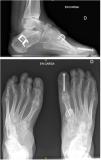

Se valoraron dos parámetros radiológicos, tanto en el período prequirúrgico como al año de la cirugía. En la proyección lateral de las radiografías simples en carga de ambos pies y tobillos se midieron los ángulos de Meary y la pendiente calcánea (fig. 1). El ángulo de Meary, entre el eje mayor del talus y el eje de M1, es una medida de la deformidad global del pie, apareciendo un pie cavo si es >4°. Si los valores son < 15° se considera leve, moderado entre 15 a 30° y severo si es >30°14. La pendiente calcánea es el ángulo entre la horizontal y una línea desde la base del talón a la cortical inferior del calcáneo, midiendo la cantidad de deformidad en cavo que depende del retropié, con valores normales entre 15 a 20°15.

Como se ha mencionado previamente, en todos los casos, la cirugía consistió en una osteotomía de ascenso del primer metatarsiano asociada a la trasferencia del tendón tibial posterior al dorso del pie (2° o 3° cuña) y a una osteotomía valguizante de calcáneo. En algunos pacientes se asociaron otros gestos quirúrgicos como alargamiento del tendón de Aquiles (mediante tenotomía percutánea), sección de la fascia plantar y musculatura corta del pie (técnica de Steindler)16, y artrodesis interfalángica del hallux o de los dedos en garra (fig. 2).

La medición radiográfica pre y postoperatoria también mostró diferencias estadísticamente significativas. El ángulo de Meary inicial era de 20,46 ± 6,13° que pasó a 13,38 ± 7,06° con una media de 6° de corrección (p < 0,005). En el caso de la pendiente calcánea pasamos de 25,30 ± 5,90° preoperatoriamente a 21,92 ± 5,66°en el postoperatotio, consiguiendo una corrección de unos 4,5° de media (p = 0,0004).